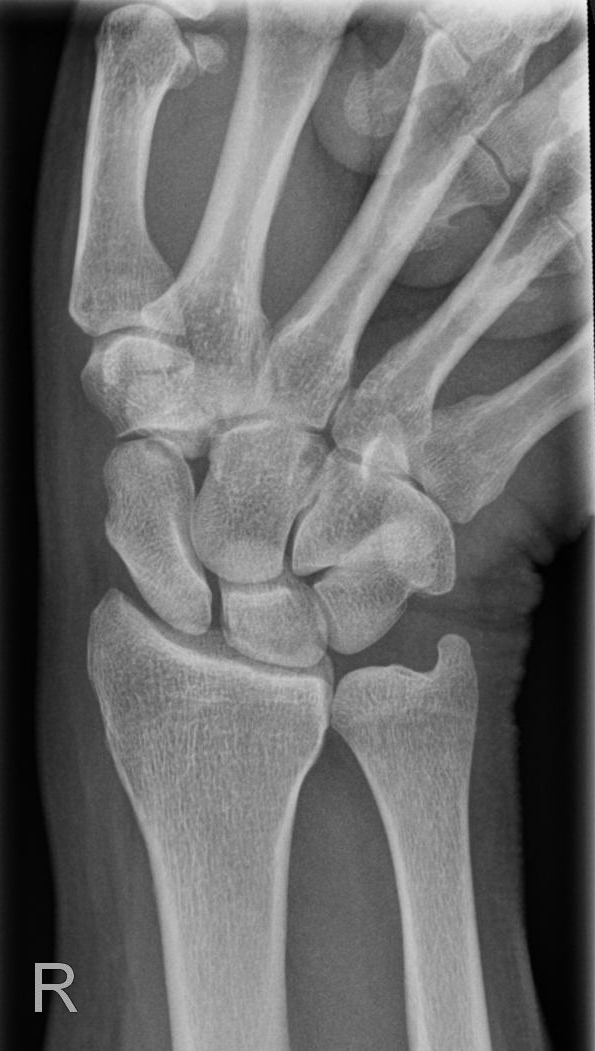

Handgelenk dorso-volar (1. Ebene)

Indikation

Fraktur

Zentralstrahl

senkrecht

Querzentrierung auf Gelenkspalt

Längszentrierung auf Objektmitte

Einblendung

distal einschließlich Fingergrundgelenke

Darstellung der Handwurzel- und Unterarmknochen, bei Fragestellung von Epiphysenlösung, Grünholz- oder Os scaphoideumfraktur. Zur Beurteilung der Knochenkerne bei Kindern werden Vergleichsaufnahmen notwendig, bei Verdacht auf Subluxation des Os Lunatums, Zusatzaufnahme in Flextion und Reflextion der Hand notwendig (siehe Stressaufnahme).

Qualitätskriterien

Vollständige Abbildung der Metacarpalia, Handwurzelknochen und distaler Unterarm.